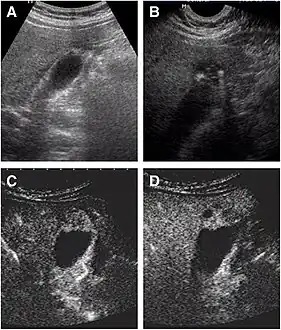

Adenomyomatosis of the gallbladder as seen on ultrasound[7]

Non-contrast abdominal ultrasound and contrast-enhanced ultrasound (CEUS) of adenomyomatosis of the gallbladder:[8]

a The fundus of the gallbladder wall was thickened and the GB wall was obscure.

b The intramural echogenic foci were detected by high frequency transducer.

c CEUS—arterial phase (22 s) —heterogeneous hyper-enhancement and wall was intact.

d CEUS—venous phase (34 s) the anechoic spaces were more clear.

Abdominal ultrasound has low accuracy in differentiating gall bladder adenomyomatosis from cancer and is operator dependent. However, it is used as the exam of the first-line due to its wide availability. Ultrasound findings may show thickened gall bladder wall, tiny anechoic spaces (Rokitansky–Aschoff sinuses or RAS), and twinkling artifact (or comet-tail reverberation). Comet tail reverberation, which is due to reflections from cholesterol crystals, is a highly specific sign for adenomyomatosis.[9]